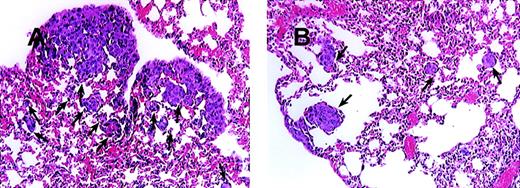

On the basis of the fact that MCP-1 is abundantly produced by tumor cells, we wanted to evaluate the contribution of MCP-1 toward tumor growth. We, therefore, selected a human breast carcinoma cell line MDA-231 to study the effect of a MCP-1 antibody on tumor growth. The MDA-231 cell line produced approximately 6500 pg of MCP-1/mL, when cells were grown at a concentration of 0.5 × 106 cells/mL of RPMI for 24 hours as determined by enzyme-linked immunosorbent assay (data not shown). MDA-231 cells were then injected intravenously into SCID mice, as described in the “Materials and methods” section. As shown in Figure 6, administration of MCP-1 antibody significantly increased the survival of SCID mice bearing MDA-231 carcinoma tumors in contrast to mice treated with control antibody (P < .024). Neither administration of exogenous MCP-1 nor antibodies to MCP-1 had an effect on the growth of MDA-231 cells in vitro (Table 2). Analysis of the metastatic lesions in the lungs revealed that the experimental micrometastases therein were significantly smaller and lower in number when treated with the MCP-1 antibody than in the control antibody group (Figure 7). As shown in Figure 8, grading analysis of the lung metastasis by calculating the total area invaded by the tumor in each mouse indicated that the group of mice treated with control antibody exhibited about 2.5 times more metastases than the group of mice treated with anti-MCP-1. The metastatic index of control-treated mice was 0.146 (SEM ± 0.027), whereas the metastatic index of anti-MCP-1–treated mice was 0.057 (SEM ± 0.011; P < .005). These data demonstrate that the size and number of metastatic lesions formed in the presence of antibody to MCP-1 are reduced, and increases in survival were observed, indicating that MCP-1 has a role in tumor progression.

Blocking of MCP-1 inhibited lung tumor metastases of SCID mice bearing MDA-231 human tumor breast cancer cells.

SCID mice were injected intravenously with 20 μL of antiserum to ASGM1 on day 0, and 3 × 105 MDA231 human breast carcinoma cells were injected intravenously on day 1. Antibodies, including rabbit IgG (panel A) and 279 Ab (Panel B) at 25 μg/mouse (1 mg/kg), were given intraperitoneally to the mice on days 4, 8, 12, 16, 20, 24, and 28. For experimental metastasis experiments, mice from both groups were sacrificed on the 35th day after intravenous injection of the tumor cells. Lungs were extracted and fixed in formalin. Histological sections were stained with hematoxylin and eosin to evaluate tumor metastases. Photographs were taken at 150× magnification. The arrows indicate metastatic lesions. One representative field from 2 experiments is shown.